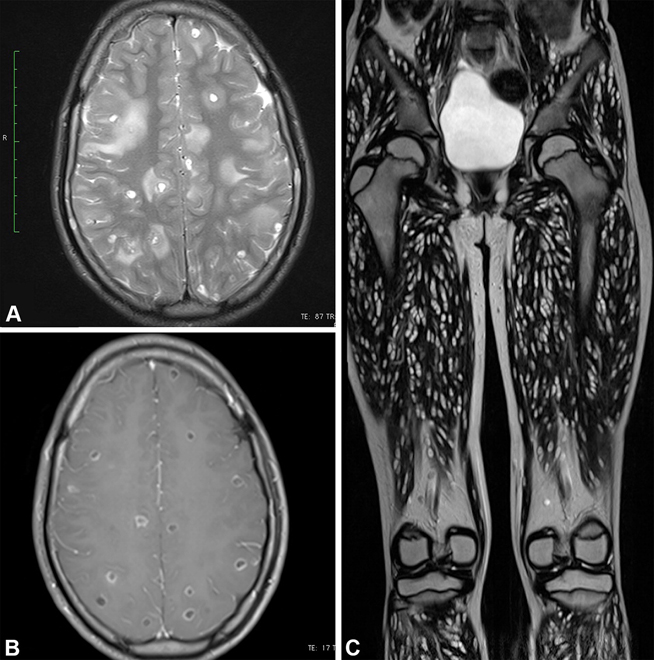

The 2024 Top Images in Radiology winner is entitled, “Disseminated Whole-Body Cysticercosis,” by Mohd Ilyas and Vikrant Mahajan. This case presents a 10-year-old female patient with generalized seizures, who underwent whole-body and brain MRI. Numerous cystic lesions in the brain, with ring enhancement and perilesional edema, together with a “rice grain” pattern of intramuscular cysts oriented parallel to muscle fibers, led to a diagnosis of disseminated cysticercosis. These striking images provoke a visceral reaction by revealing the body overwhelmed with parasites. At the same time, they teach readers the pathognomonic appearance of this entity, with multifocal small round cysts in the brain and oblong cysts in the muscles. This article was downloaded nearly 20,000 times and achieved an Altimetric score in the top 5% of all research outputs of the same age.